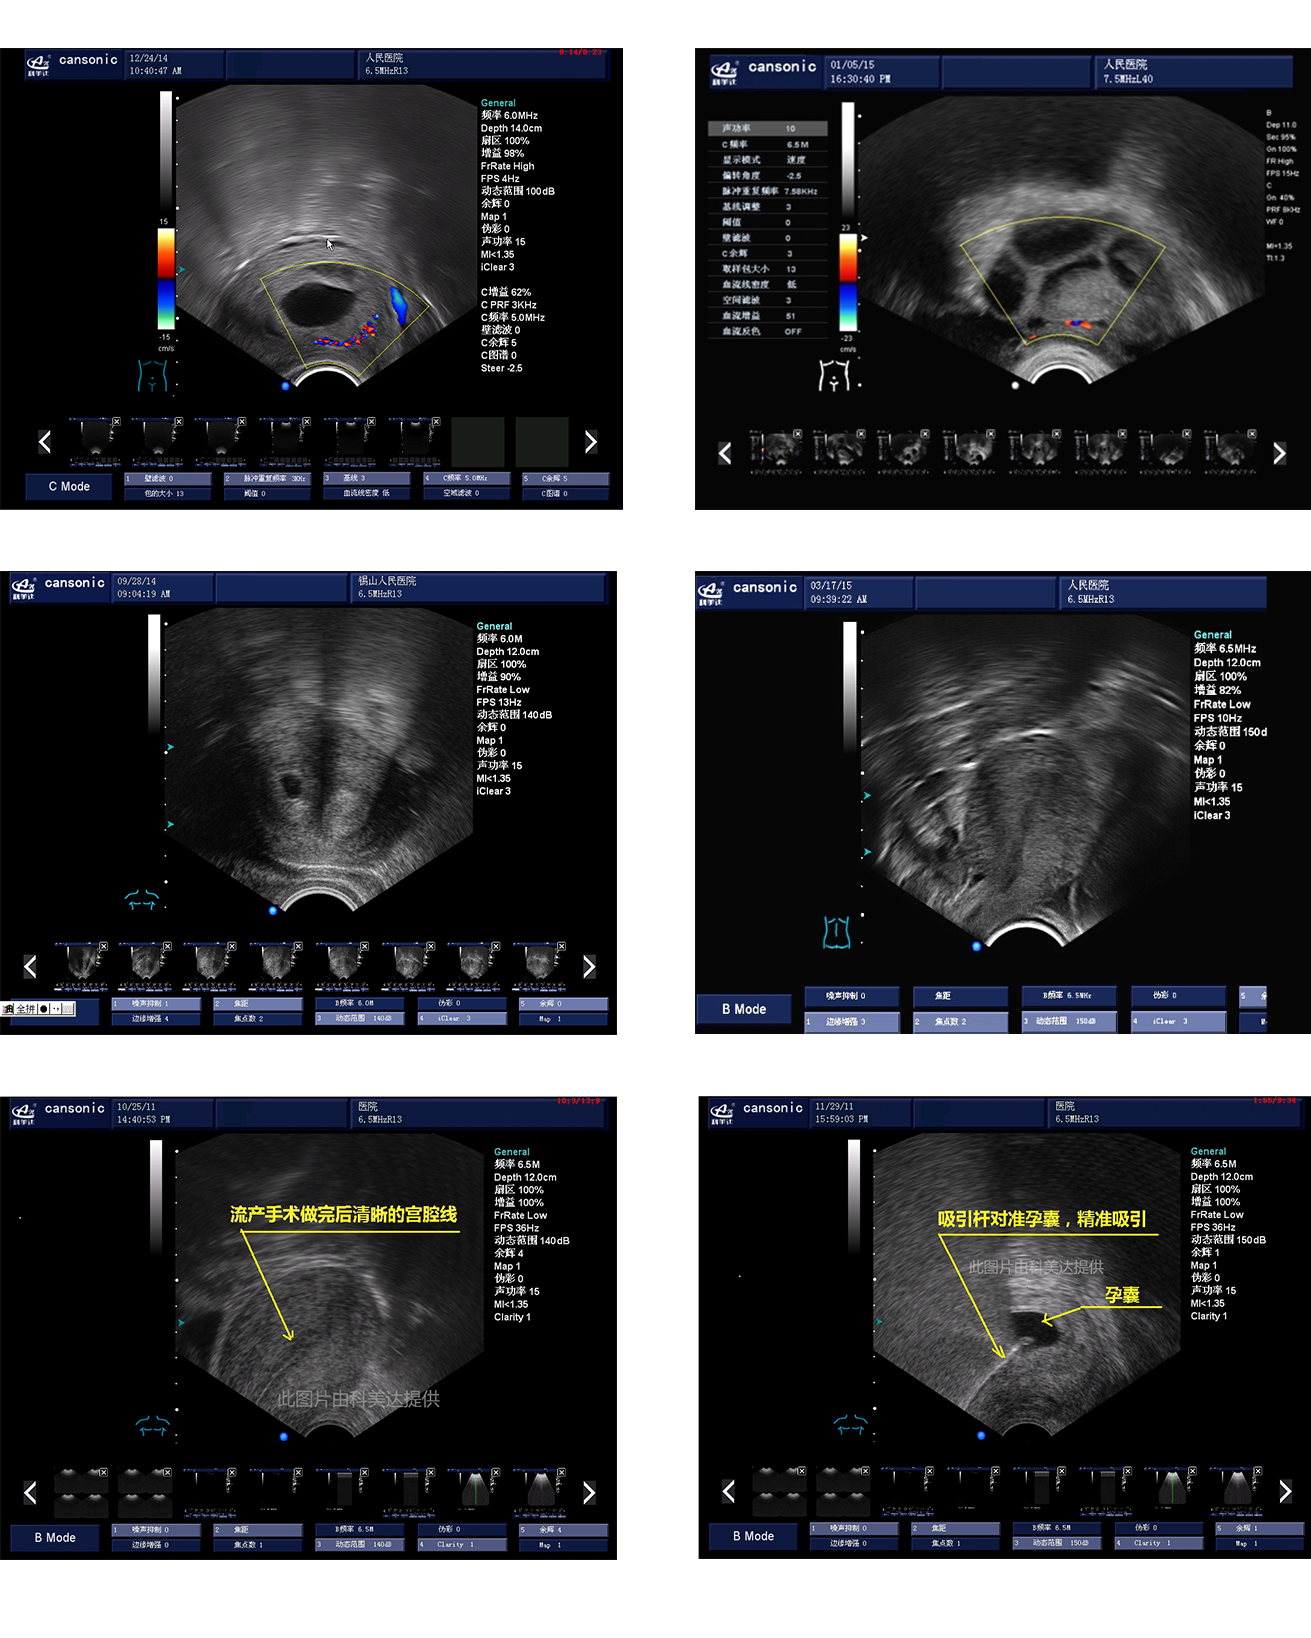

臨床圖示

1、融合業(yè)內(nèi)高端的硬件工藝及智能后處理算法,結(jié)合規(guī)范的操作流程,實(shí)現(xiàn)對(duì)宮腔手術(shù)的全程監(jiān)測

2、精準(zhǔn)數(shù)字濾波技術(shù),有效降低多普勒噪聲及運(yùn)動(dòng)偽像,提升血流及多普勒超聲圖像

4、能量多普勒POWER成像模式彩色多普勒Color成像模式

5、血流靈敏度高,清晰可見